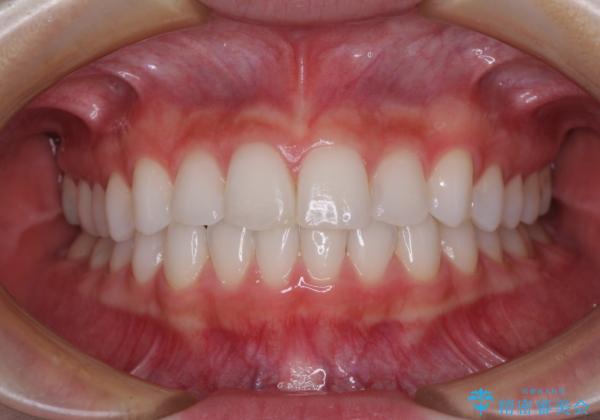

矯正治療は8ヶ月ほどで終了し、速やかに虫歯治療に移行することができました。

保険治療で用いる樹脂(コンポジットレジン)で行った虫歯治療は、周辺が変色して汚くなっていましたが、下顎はセラミックインレーで審美的に、上顎はPGAインレーで歯に負担の少ない治療を行うことができました。